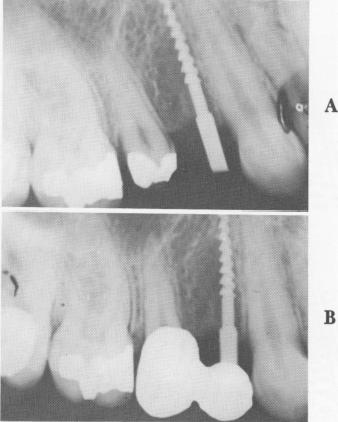

The titanium screw post, designed by Michel Chercheve for a narrow ridge, is threaded along most of the shaft (Fig. 5-64). Above the threaded part is a fairly long, narrow neck that extends from the alveolar crest through the mucosa. Uppermost is a square head that fits exactly into a hand ratchet so that the implant may be worked into the bone, not driven into it. When the implant is in place, its protruding head is bent so that it is parallel to pre-pared teeth and to the abutment posts of other implants (Fig. 5-65).

Fig. 5-64. The Michel Chercheve narrow ridge implant inserted by Linkow. A, The implant just after insertion; B, the prosthesis in place.